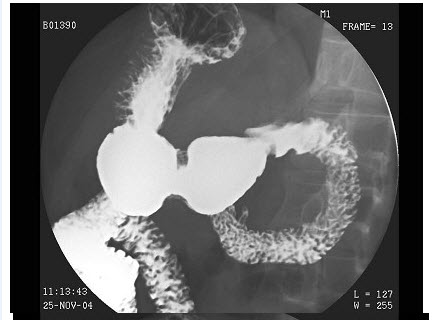

15、单项选择题

男,48岁,吞咽不适、返酸3年,结合图像,最可能的诊断为()

A.正常肠圈

B.十二指肠炎

C.球部溃疡

D.降段憩室

E.水平段憩室